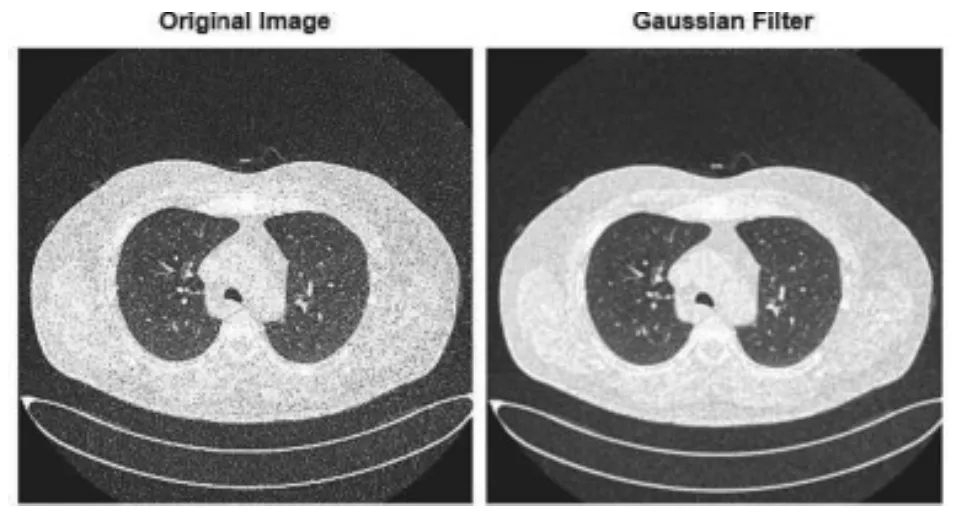

Gaussian Noise in Real-Life

Modern AI solutions frequently apply Gaussian Noise augmentation in medical image analysis, especially in MRI and CT scan segmentation. Introducing noise during training helps models adapt to variations caused by different scanner types and acquisition settings. This improves generalization across diverse datasets, leading to more reliable diagnostic tools.

Source

Take a lung nodule detection system trained only on clean images. It may struggle when faced with real-world scans that naturally contain acquisition noise. A similar issue arises when training when test datasets come from scanners with different settings. Adding Gaussian Noise acts as a form of "averaging," helping the model focus on essential features despite noise. This enhances model accuracy across varied datasets.

The effectiveness of this approach isn't just theoretical. A recent study published in Artificial Intelligence Review demonstrated that augmentation methods, including Gaussian noise addition, significantly improved the accuracy of tumor segmentation and classification algorithms.

The practical value of noise augmentation is further validated through competitive benchmarks like the Ultrasound Nerve Segmentation Challenge and UW-Madison GI Tract Image Segmentation competition on Kaggle, where top-performing solutions frequently employ noise augmentation strategies.